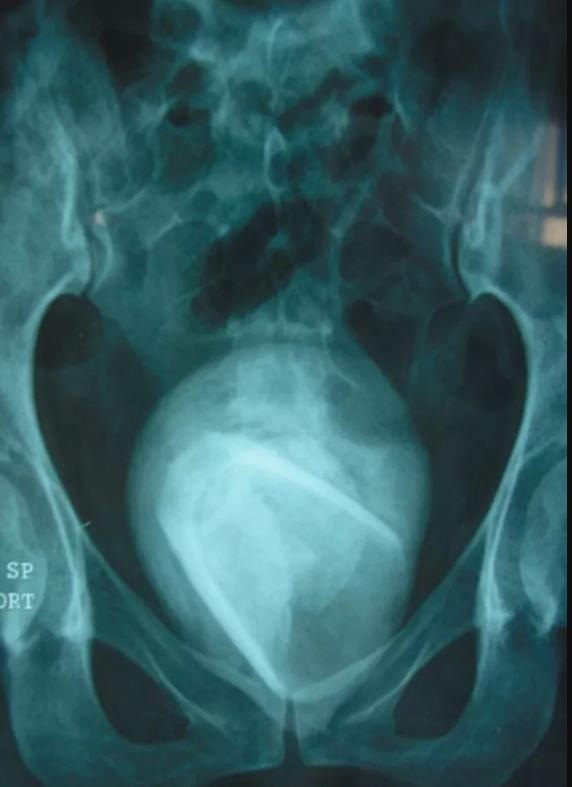

Fantezi merakı 45 yaşındaki kadının günlerce hastanede kalmasına neden oldu. İdrar yolu ağrısı şikayeti ile doktora başvuran kadının çekilen röntgeninde mesanede cam bardak olduğu görüldü.

İdrar yolları enfeksiyonu şikayetiyle hastaneye başvuran kadının röntgen filmi çekildikten sonra ortaya çıkanlar görenlerin ağızlarını açık bıraktı. 45 yaşındaki Tunuslu kadının mesanesinden cam bardak çıktı. İçki bardağı olduğu tahmin edilen bardağın 4 yıldır kadının içinde olduğu öğrenildi.

Taramalar sonucu öncelikle vücudun bir enfeksiyonla savaştığı ortaya çıktı. Yapılan röntgen çekimi sonrası ise cam tespit edildi. Yıllardır duran camın dışı zaman içinde mesane taşıyla çevrildiği için hemen fark edilemedi.

Kadının mesanesindeki cam idrar yollarını tıkadığı için yıllar içinde bardağın etrafı sert mineral kütleler tarafından örtülmüştü. Doktorlar hem mesane taşını hem de 4 yıldır orada duran bardağı çıkarmak için hastayı ameliyata aldı.